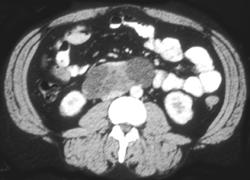

Bladder Cancer Obstructs the Left Ureter